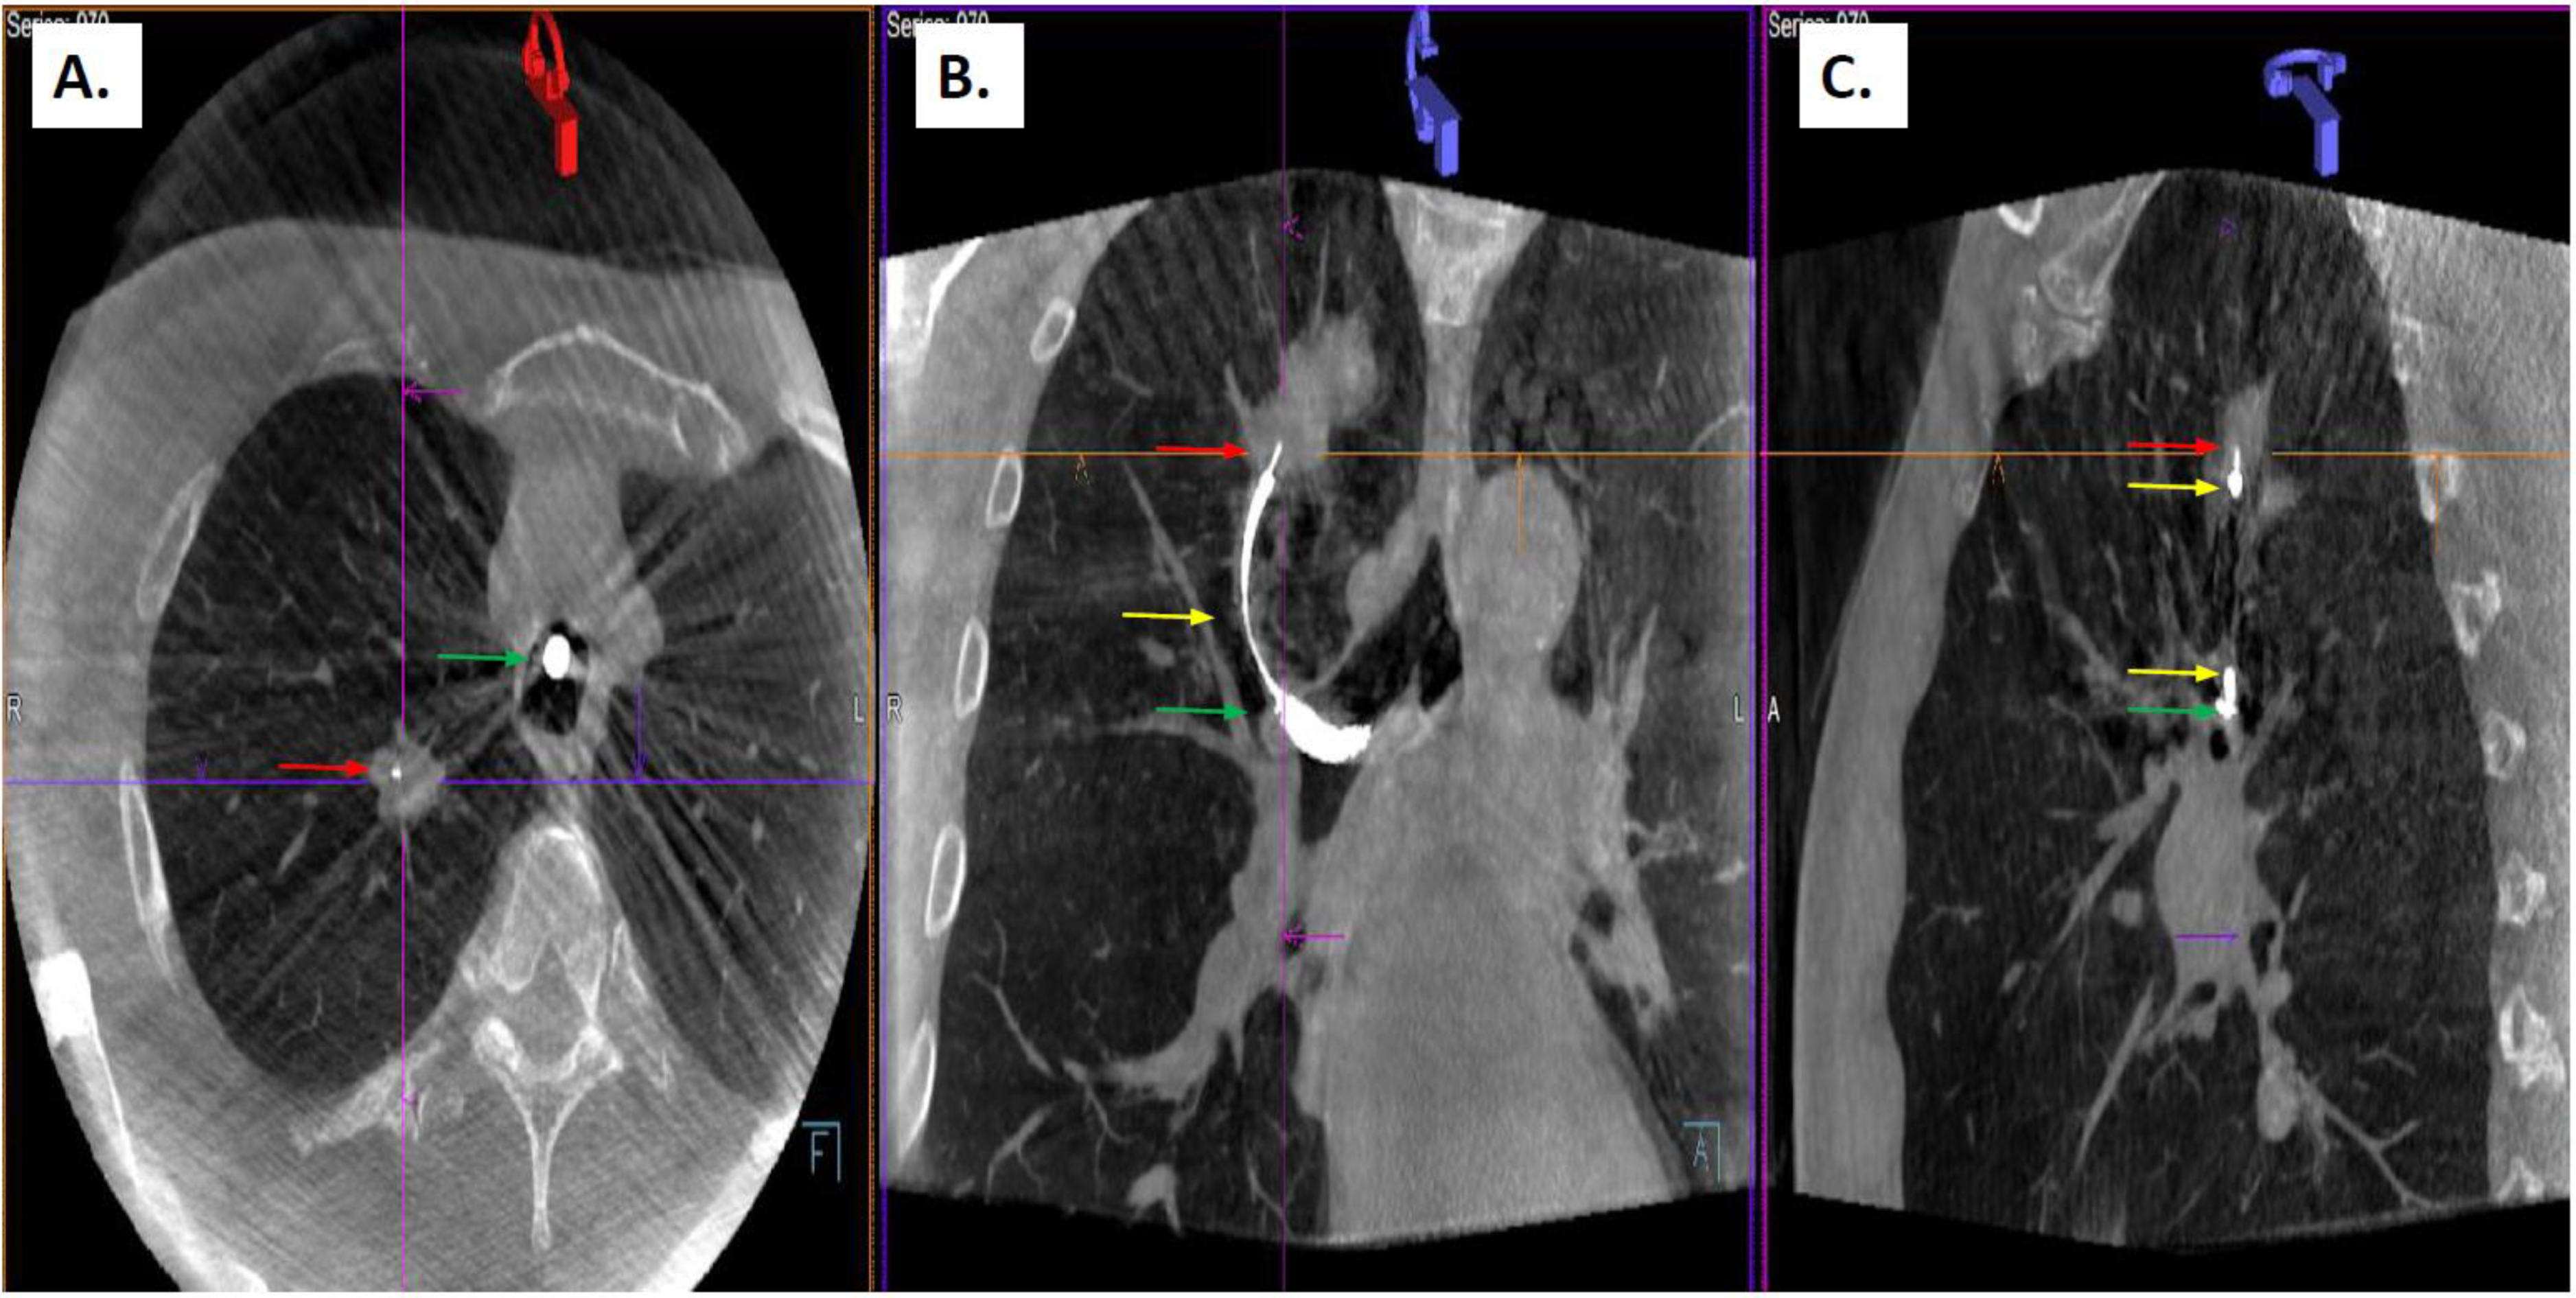

2.2. Procedure Description